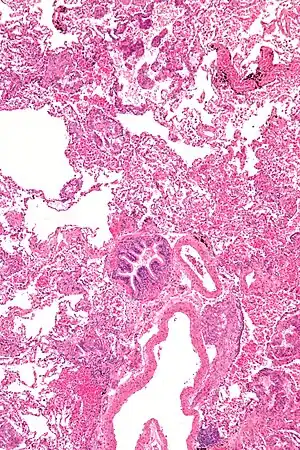

A linfangioleimiomatose (LAM) é uma rara doença intersticial pulmonar idiopática que afeta exclusivamente mulheres, tipicamente durante seus anos reprodutivos, caracterizada pela proliferação anormal de células de músculo liso nos pulmões e nos linfáticos retroperitoneais e torácicos. [1]